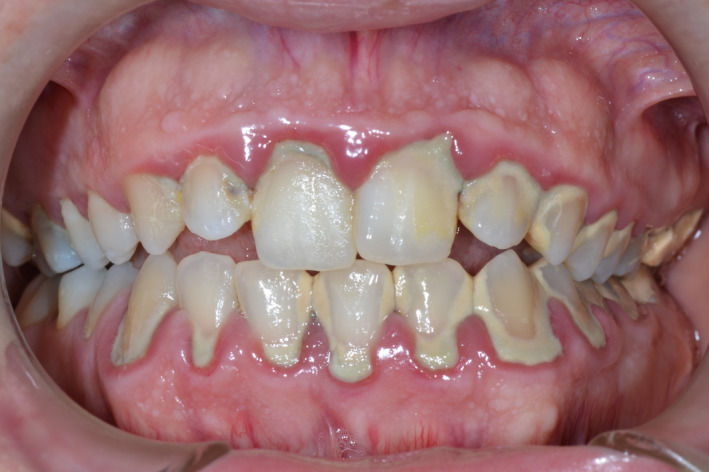

FIGURE 3.

Clinical presentation of a 20‐year‐old Caucasian male patient with plaque‐induced gingivitis and cannabis‐induced gingival enlargement

Another frequent, interesting clinical observation is the association between chronic use of cannabis and gingival enlargement (Figure 3). Several authors 35 , 40 , 58 have reported cases of marijuana‐associated gingival enlargements. It appears that marijuana‐associated gingival enlargement is a condition seen primarily in young adult males who have had 2 or more years of continuous marijuana consumption. 40 The gingival enlargements are mostly papillary and marginal, comparable with the gingival enlargement that occurred with phenytoin (dilantin) therapy, where the areas primarily affected are the interdental papillae and the marginal gingiva; sometimes they appear to be nodular. 59 , 60 There may be a biochemical basis for the clinical similarities between marijuana‐associated and phenytoin‐induced gingival enlargement. Cannabidiol is a major nonpsychotropic constituent of cannabis. As indicated above, attention has been focused on its pharmacologic aspects over the past few years because of its anticonvulsive, anxiolytic, antipsychotic, antiemetic, and antiarthritic properties. 61 Considering the common anticonvulsant properties and the similarity in structure between cannabidiol and phenytoin, it may be hypothesized that the enlargement seen in marijuana users is caused by pathogenetic mechanisms similar to those implicated in phenytoin‐induced gingival enlargement. These include an increase of gingival fibroblast growth and connective tissue matrix production, inflammation, and altered effects on calcium metabolism in a complex epigenetic interactive environment. 62